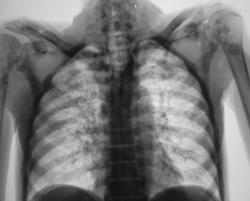

Метастазы. Наблюдение Владимира Борисовича Серова.

Метастазы. Наблюдение Владимира Борисовича Серова.

Множественные метастазы.